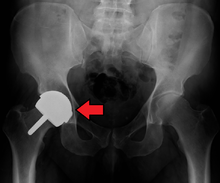

Metal sensitivity

Concerns are being raised about the metal sensitivity and potential dangers of metal particulate debris. New publications[5][6] have demonstrated development of pseudotumors, soft tissue masses containing necrotic tissue, around the hip joint. It appears these masses are more common in women and these patients show a higher level of iron in the blood. The cause is unknown and is probably multifactorial. There may be a toxic reaction to an excess of particulate metal wear debris or a hypersensitivity reaction to a normal amount of metal debris.

Metal hypersensitivity is a well-established phenomenon and is common, affecting about 10–15% of the population.[7] Contact with metals can cause immune reactions such as skin hives, eczema, redness and itching. Although little is known about the short- and long-term pharmacodynamics and bioavailability of circulating metal degradation products in vivo, there have been many reports of immunologic type responses temporally associated with implantation of metal components. Individual case reports link hypersensitivity immune reactions with adverse performance of metallic clinical cardiovascular, orthopedic and plastic surgical and dental implants.[7]